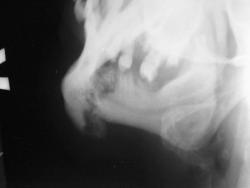

Вот один из них.

Валентин Львович! Результат налицо. Открытый перелом в области 8-го зуба. И на противоположной стороне в области 2-3-го зубов.

Переломы: через лунку 8 с одной стороны, с другой - в обл 3/4.

Замечания: не маркирована сторона, не достаточно косой снимок - наложение сторон. Стоило снять с двух сторон.